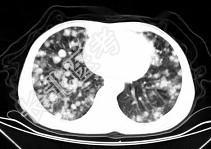

- 单项选择题男,42岁, 肝区痛一月余,最近二周咯血丝痰, 胸部CT如图,最可能的诊断为 ( )

D、肺转移瘤